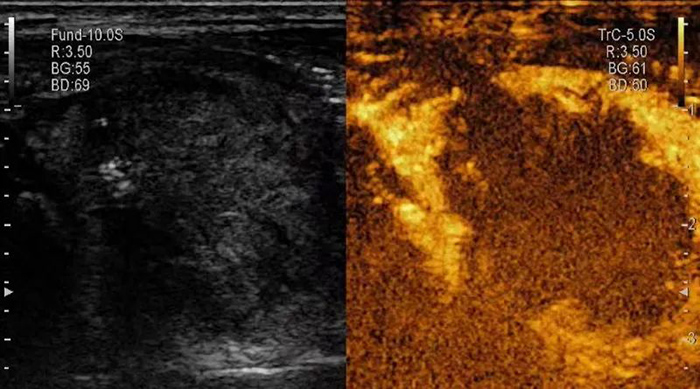

▲消融后,超声造影提示结节内完全无增强,呈“黑洞征”,表明肿瘤被完全杀死。